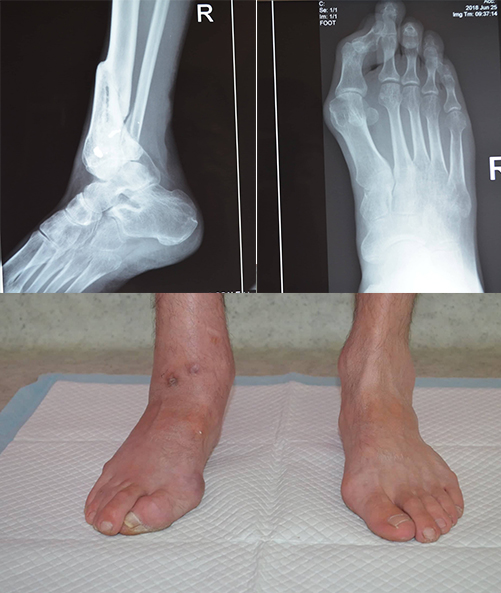

При наступанні на ногу Сергій відчуває сильні болі, гомілка наче розколюється навіл, а великий палець вже майже зайшов під стопу. Болі дедалі посилюються.

Діагноз Сергія: варусно-антикурваційна деформація гомілки.

З метою повернення нозі Сергія опороздатності лікар планує виконати два етапи лікування - зробити остеотомію та остеосинтез по Ілізарову для усунення деформації великогомілкової кістки та зробити артродез зруйнованого гомілково-ступневого суглобу. Вартість лікування становить 98 796 грн.